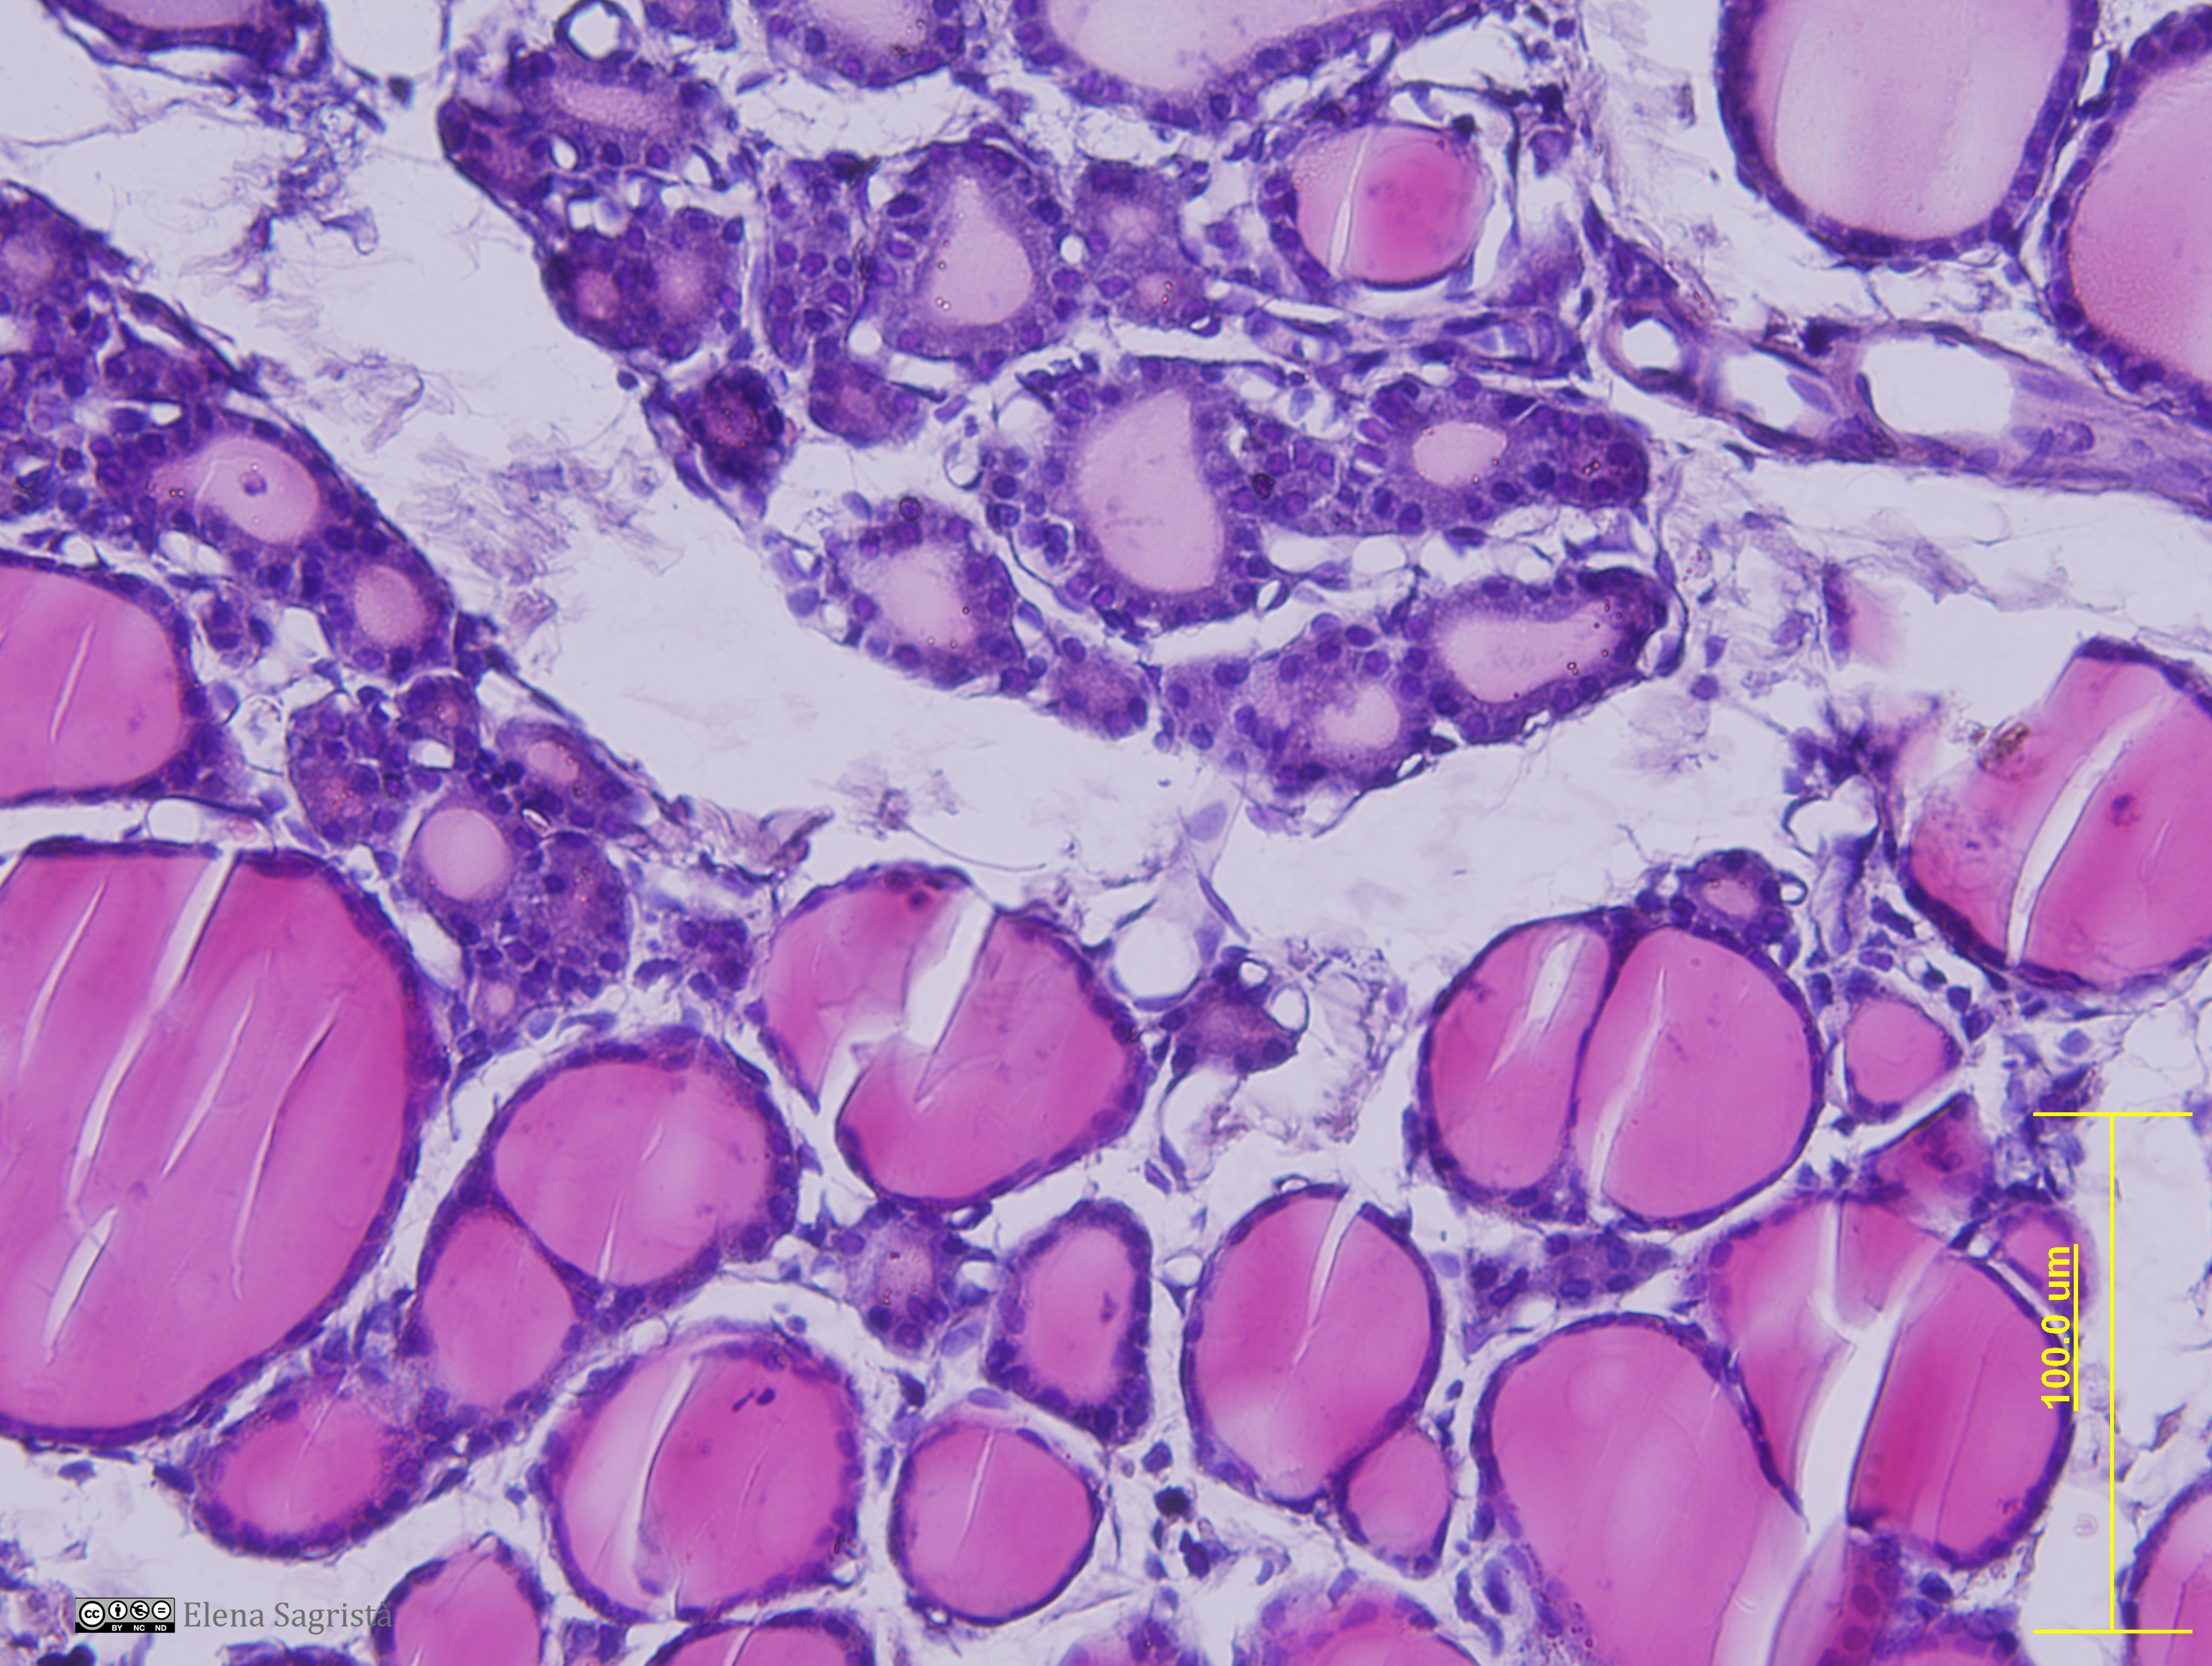

Histologia imatges: 01 Teixit epitelial

Imatges de preparacions histològiques de teixit epitelial. Microscopia òptica.